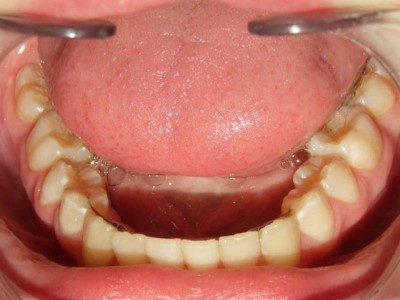

Voor behandeling